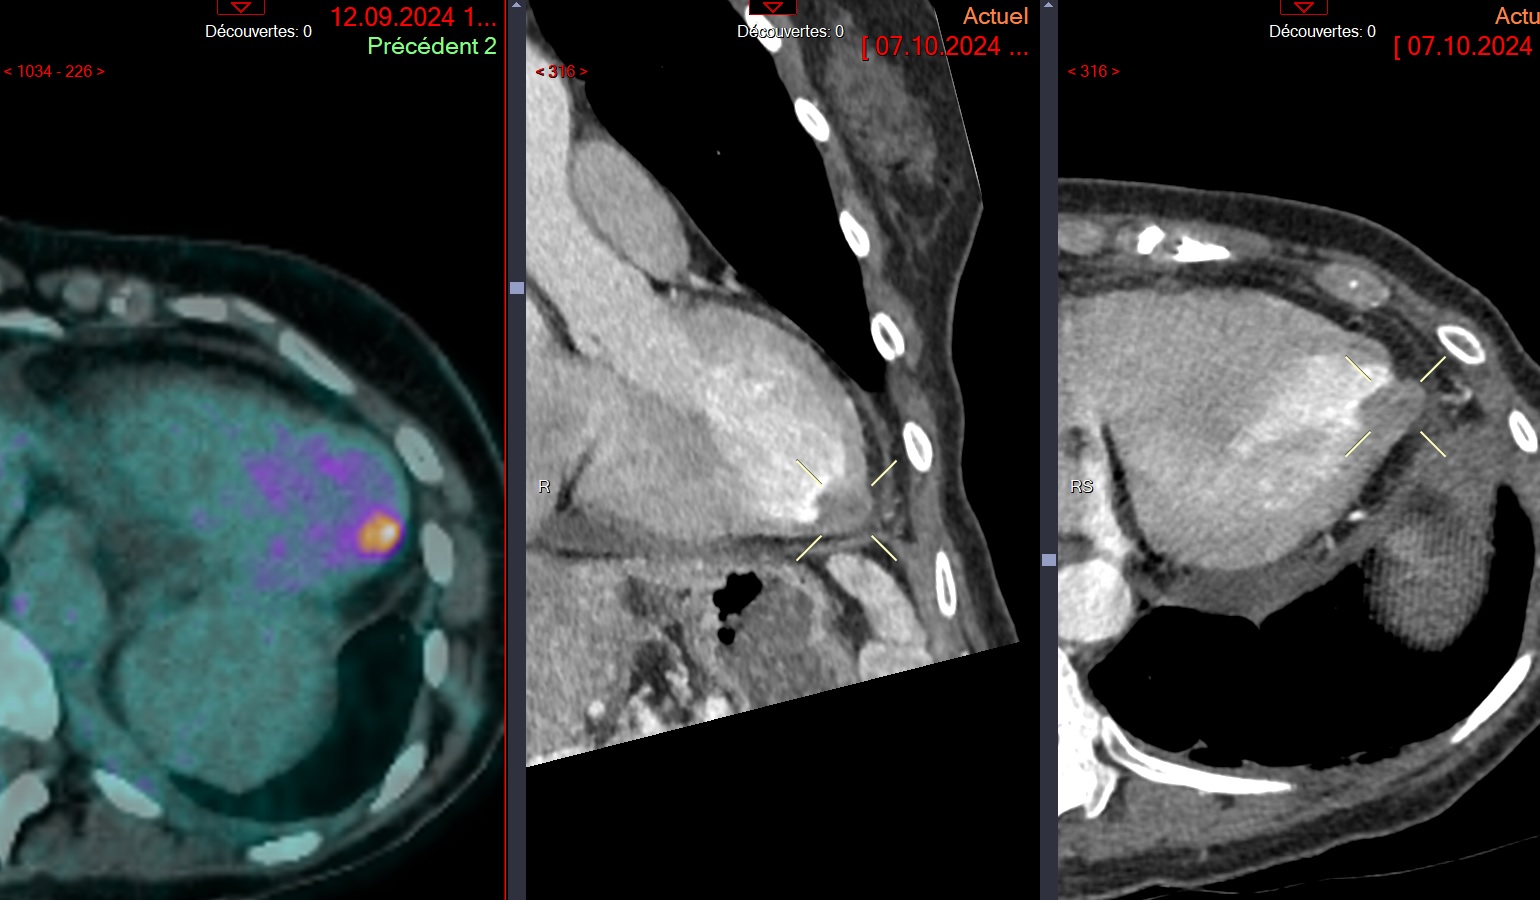

Metastase myocardique melanome progressif

Metastase myocardique melanome progressif